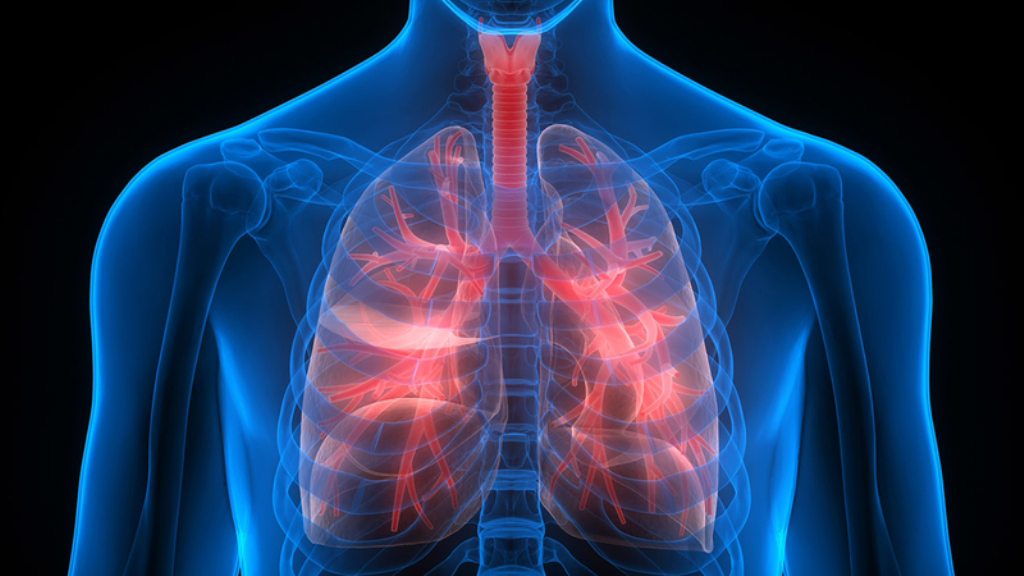

यदि बिरामी आफैं वा हेरचार गर्ने व्यक्तिको सहायतामा बस्न सक्छ भने श्वास प्रश्वास र फोक्सोको चालमा मद्दत पुर्याउने अन्य आसन वा तरिका पनि अपनाउन सकिन्छ। फिजियो थेरापिष्ट वा नर्सले श्वासप्रश्वाससँग सम्बन्धित व्यायामहरु सिकाउनेछ।

श्वासप्रश्वासको व्यायामले फोक्सोलाई फैलाउन मद्दत पुर्याउँछ। श्वासप्रश्वास गतिमा सुधार ल्याउँछ फोक्सोमा जमेको खकारमा हलचल पैदा गरी निकाल्न सजिलो बनाउँछ।

पेटमा हातले हलुका थिच्दा फोक्सोमा हावा भरिएको महसुस गर्न मद्दत पुयाउँछ।

नाकबाट फोक्सोभित्र हावा तान्ने र मुखबाट हावा छोड्ने।

खोक्ने अभ्यास गर्नु भन्दा १० मिनेट अगाडि बिरामीलाई तातोपानी बाफ लिन लागाउनुपर्छ। यसले फोक्सो र श्वासप्रश्वास नलीमा भएका नरम बनाई निकाल्न मद्दत गर्छ।

श्वासप्रश्वास नलीको संक्रमण भएको बिरामीले भित्रैदेखि बिस्तारै गहिरो सास तान्ने र छोड्ने पक्रिया प्रसस्त मात्रामा नगरेमा उसको फोके झन कमजोर हुन जान्छ। तर बिरामी कमजोर छ, भित्रैदेखि गहिरो सास तान्न छोड्न वा फेर्न नसक्ने अवस्थाको भएमा सास फेर्ने मेसिन स्पाइरोमिटरको प्रयोबाट श्वासप्रश्वास गराउन सकिन्छ। यसले फोक्सोलाई स्वास्थ्य बनाई राख्न मद्दत पुर्याउँछ। यस मेसिनबाट बिस्तारै सास तान्ने छोड्ने तरिका पनि सिक्न सकिन्छ।

सास फेर्ने मेशिन स्पाइरोमिटरको प्रयोग गरी प्रत्येक १देखि२ घन्टामा १०,१५ पटक सास फेर्ने गर्नुपर्छ । वा जिजियोथेरापिष्टको निर्देशनअनुसार राख्न र निको हुन सक्रिय हुनुपर्छ।